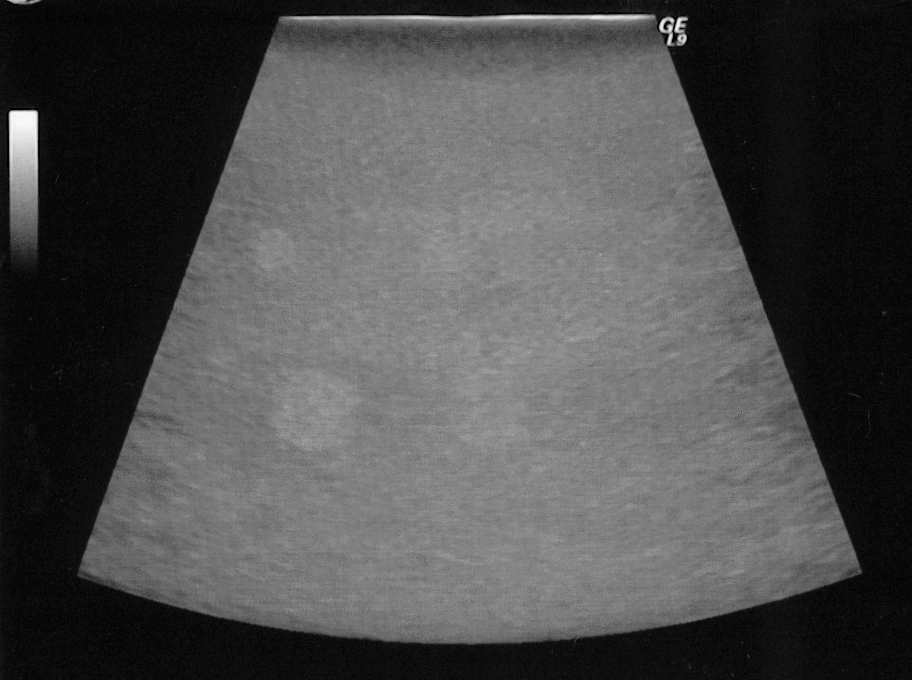

病变检出能力是超声成像设备临床有效性关键特性之一,而表达这一特性是低对比度显示能力,是区别两种不同组织的主要手段,对于脏器来说,当病变刚刚发生时,其在超声影像上,与正常的组织区别很小,因此,B 超的性能越好,其区别细微差别的组织的能力就越强。

谐波成像是近些年发展起来的,在临床上获得广泛的应用,谐波成像可以较大幅度地提高组织的对比度,从而更清晰地分辨出病变。